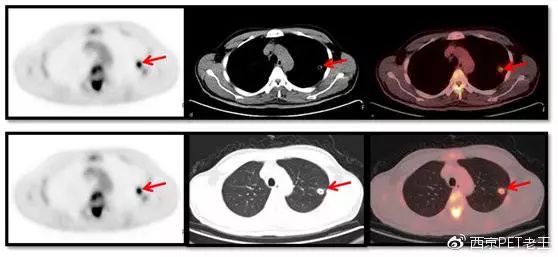

我们又发现了这么多的骨转移病变,那原发病灶究竟在哪里呢?我们仔细寻找,在左肺上叶发现了一个空洞样病变,边缘见细毛刺及胸膜牵拉征,呈葡萄糖代谢异常增高,我们考虑为恶性病变(肺癌?),如下图:

左肺上叶发现了一个空洞样病变(红色)

我们给出的结论:左肺上叶肺癌伴肝脏、骨广泛性转移。